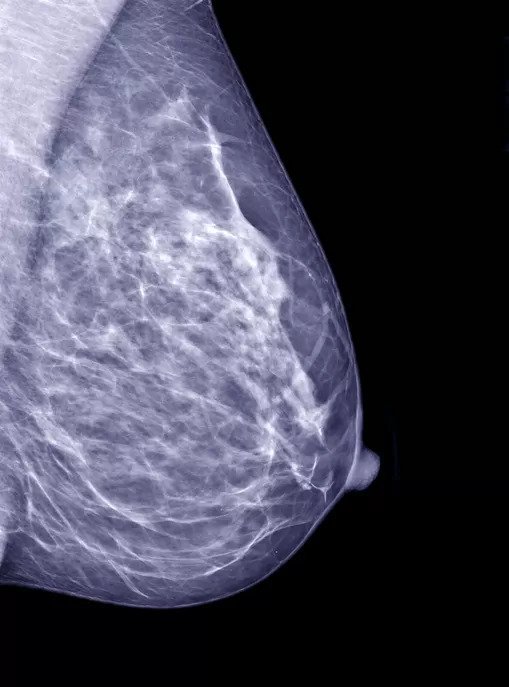

Mammograms are an essential screening tool for breast cancer. They use low-dose X-rays to produce images of the breast tissue, which can help detect breast cancer in its early stages. If you're scheduled for a mammogram, here's what you can expect during the procedure.

During the mammogram procedure, you'll stand in front of a mammography machine, which will compress your breast between two plates. This may cause some discomfort, but it usually only lasts for a few seconds. The technician will take images of your breast from different angles to ensure accurate imaging.

After the mammogram procedure, a radiologist will analyze the images and report the results to your doctor. If any abnormalities are found, you may need to undergo additional testing, such as a breast ultrasound or biopsy.